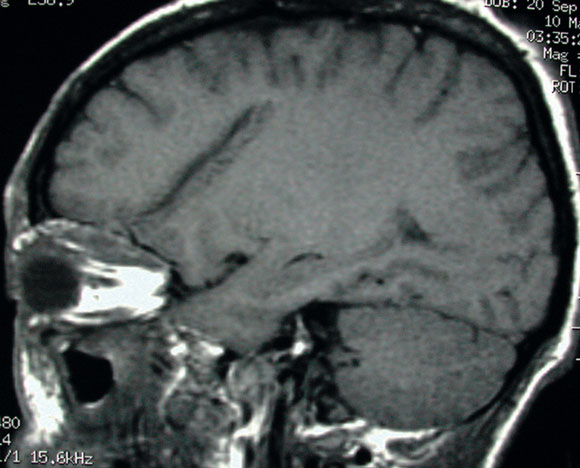

Non-contrast computed tomography (CT) of the brain revealed two minute areas of high density in the left frontal lobe, interpreted as evidence of early infection. CT of the orbits revealed left-sided swelling of the subcutaneous soft tissue, interpreted as preseptal cellulitis. A fracture of the left orbital roof was also noted adjacent to a superior orbital phlegmon (Box 1A).

However, as the cerebrospinal fluid appeared normal on microscopy and biochemical examination and showed no growth on culture, the initial diagnosis was questioned. Magnetic resonance imaging of the brain and orbits was performed the day after presentation. This showed a 5 cm tract extending obliquely from the roof of the left orbit into the white matter of the left frontal lobe, associated with a fracture of the orbital plate of the frontal bone (Box 1B). Inflammatory changes, presumed infective, were noted superiorly within the left orbit, resulting in proptosis.

1 Imaging in a patient with an orbital fracture

A. Computed tomography showed a fracture of the roof of the left orbit (F), adjacent to a superior orbital phlegmon (P).

B. Subsequent magnetic resonance imaging showed a 5 cm oblique tract extending from the fracture of the orbital plate of the left frontal bone into the white matter of the left frontal lobe.